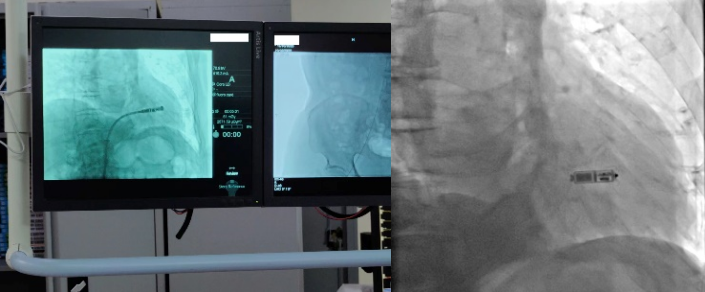

2022年11月16日,心血管内科三病区心脏介入团队在科主任孙林教授指导下,成功完成一台新一代双腔无导线起搏器植入术,通过右侧股静脉在患者心脏内“扎根”,让患者重获“心”生。

无导线起搏器是一种新兴的心脏起搏器,让“不开刀即可安装起搏器”的梦想成为现实。它身形小巧,只有胶囊大小,重仅2克。但却拥有超强的电池续航能力,寿命超过12年。同时兼容1.5T/3.0T核磁共振扫描,可满足患者之后疾病诊断需求。与传统心脏起搏器相比,双腔无导线起搏器体积减少93%,整个手术过程时间短,植入成功率高。可以保存心房、心室的顺序收缩功能,实现生理性起搏功能,开启了“无导线起搏新时代”。该技术的成功开展,是亚洲色吧 心血管内科三病区不断开展新技术、持续提升服务水平的生动注脚。未来,心血管内科将持续推进该项技术的普及,为更多患者的“心健康”保驾护航。